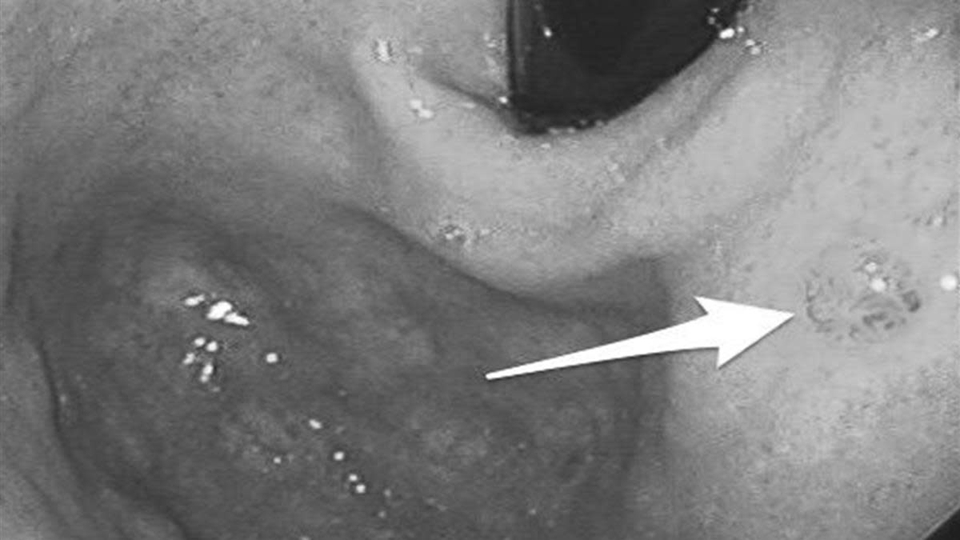

Thực tế, dạ dày không “bỗng nhiên hỏng”. Trước khi chuyển biến xấu, cơ quan này thường phát tín hiệu cảnh báo trong thời gian dài, nhưng vì triệu chứng mơ hồ, nhiều người dễ bỏ qua. Đáng lo hơn, không ít trường hợp chỉ phát hiện khi nội soi, lúc đó nguy cơ đã bước sang giai đoạn trung hoặc muộn.

Theo Cơ quan Nghiên cứu Ung thư Quốc tế (IARC), bệnh thường tiến triển qua một quá trình dài: viêm mạn tính, tổn thương niêm mạc, tăng sinh bất thường rồi mới chuyển thành ung thư.

Cơ chế này chịu tác động của nhiều yếu tố. Nhiễm vi khuẩn Helicobacter pylori (HP), ăn mặn kéo dài hoặc thói quen sinh hoạt thất thường đều có thể làm suy yếu lớp bảo vệ niêm mạc dạ dày. Khi quá trình tổn thương và sửa chữa lặp lại nhiều lần nhưng không hoàn chỉnh, niêm mạc có thể xuất hiện “chuyển sản ruột” - một dạng tổn thương tiền ung thư.

Các tổng quan trên tạp chí The Lancet Oncology cho thấy nếu can thiệp từ giai đoạn tiền ung thư, tiên lượng có thể cải thiện hơn 50%. Tuy nhiên, điểm khó là giai đoạn này hầu như không gây đau dữ dội, mà chỉ là những thay đổi nhẹ, dễ bị xem nhẹ.